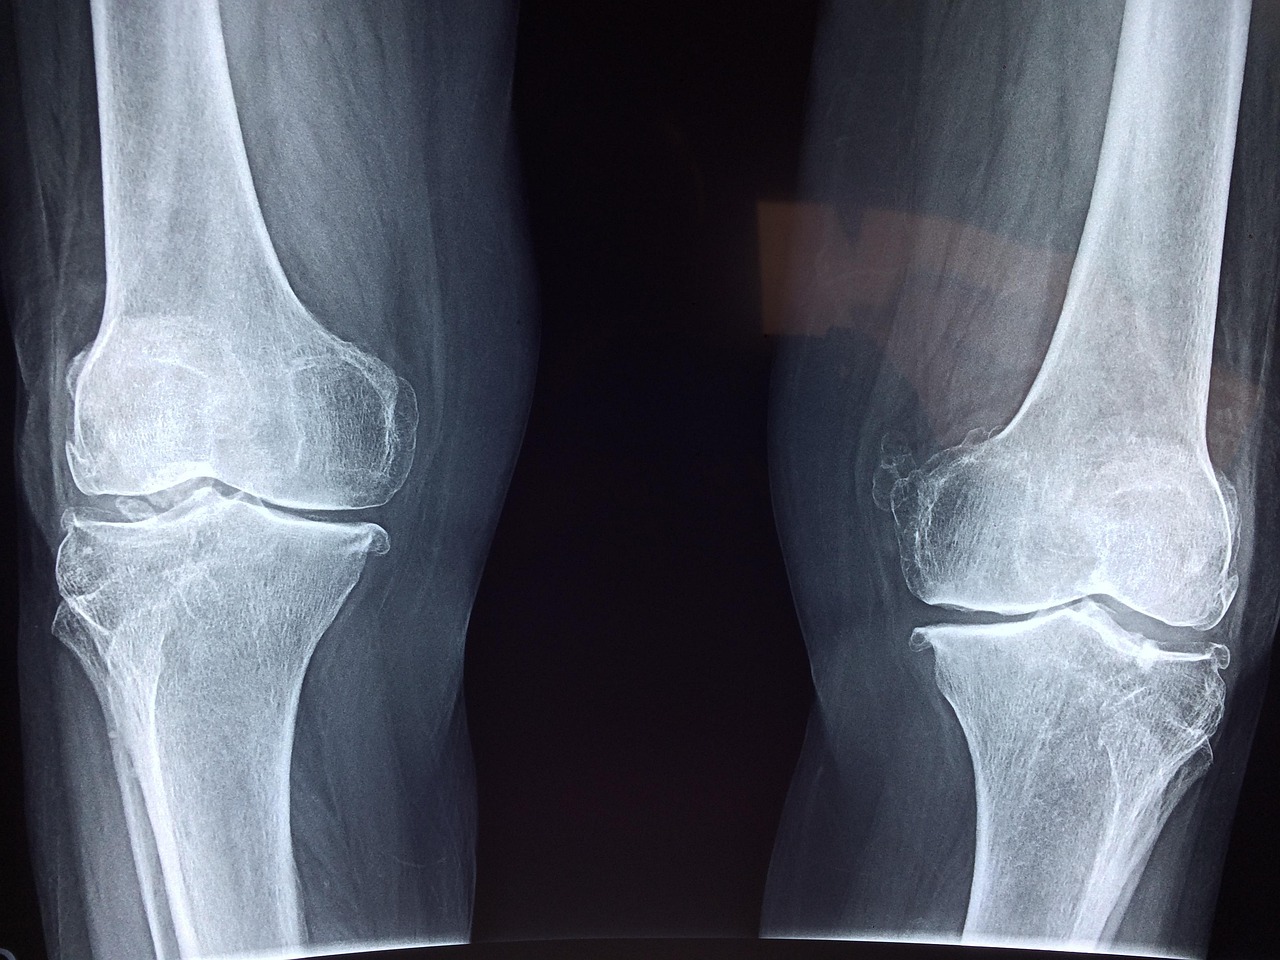

Bone diseases represent a significant concern among athletes and competitors, particularly in the skeleton sport. These conditions can impede performance, leading to potential injuries. With the advent of advanced imaging technologies, diagnosing bone-related ailments has become increasingly efficient and accurate. Traditional methods, such as X-rays, often fail to detect subtle stresses or hairline fractures that may affect athletes over time. New imaging techniques, like MRI and CT scans, reveal detailed images of bone structures, providing essential insights into diagnosis. The analysis of these images allows clinicians to identify conditions like osteoporosis or fractures more effectively. Early detection through imaging not only prolongs an athlete’s career but also ensures better management of their overall health. Integrating this technology into regular check-ups for sports professionals can enhance preventative care. This proactive approach is vital in a field where physical demands are high. A combination of imaging technologies and expert evaluations plays an influential role in maintaining optimal bone health. With continuous advancements, imaging remains a critical tool for any competitive skeleton athlete, facilitating early interventions and tailored rehabilitation protocols to enhance recovery and performance.

Computed Tomography (CT) is another potent imaging technique that has begun to make significant inroads into the assessment of bone diseases among skeleton athletes. CT scans offer high-resolution images which allow for a thorough examination of bone structures, revealing intricate details not accessible through other imaging techniques. This level of detail is particularly useful in identifying complex fractures and degenerative diseases that could otherwise go unnoticed. For athletes engaged in high-stress sports, such as skeleton racing, this information is paramount. The ability to visualize the condition of bones can help medical professionals devise tailored treatment plans. Furthermore, CT imaging can guide the rehabilitation process, ensuring athletes can safely return to their sport after injury or surgery. While CT does involve exposure to radiation, advancements in technology have significantly reduced the doses required for imaging. Thus, the benefits often outweigh the risks, especially when dealing with serious injuries. The integration of CT scans into routine assessments enhances the overall diagnostic protocol, elevating healthcare standards for competitive athletes. The continual evolution of imaging technologies will likely yield even better diagnostic and treatment modalities for bone health and performance.